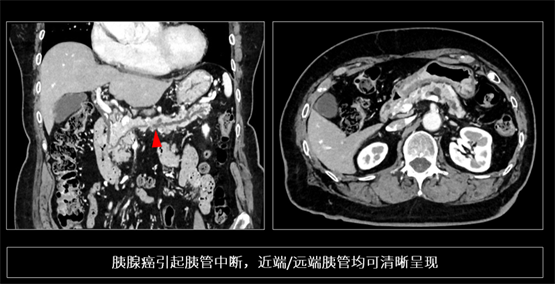

胰腺癌被称为“癌中之王”,早期病灶往往呈现等密度,且解剖位置深,极易漏诊。传统 CT 因软组织对比度与分辨率的相互制约,难以捕捉胰管的微小截断或局限性狭窄。依托 PIQE 的高空间分辨率与低噪声特性,INSIGHT Pioneer 能够捕捉到胰腺实质的细微纹理改变及胰管的早期形态学变化。在一位早期胰腺癌患者的影像(下图)中,胰管出现细微中断,且上下游胰管呈现连续而清晰的形态,基于这一隐匿性病变的识别,临床在进一步检查中将其证实为早期胰腺癌。这样的胰管变化,在传统 CT 上几乎不可能这么清楚。